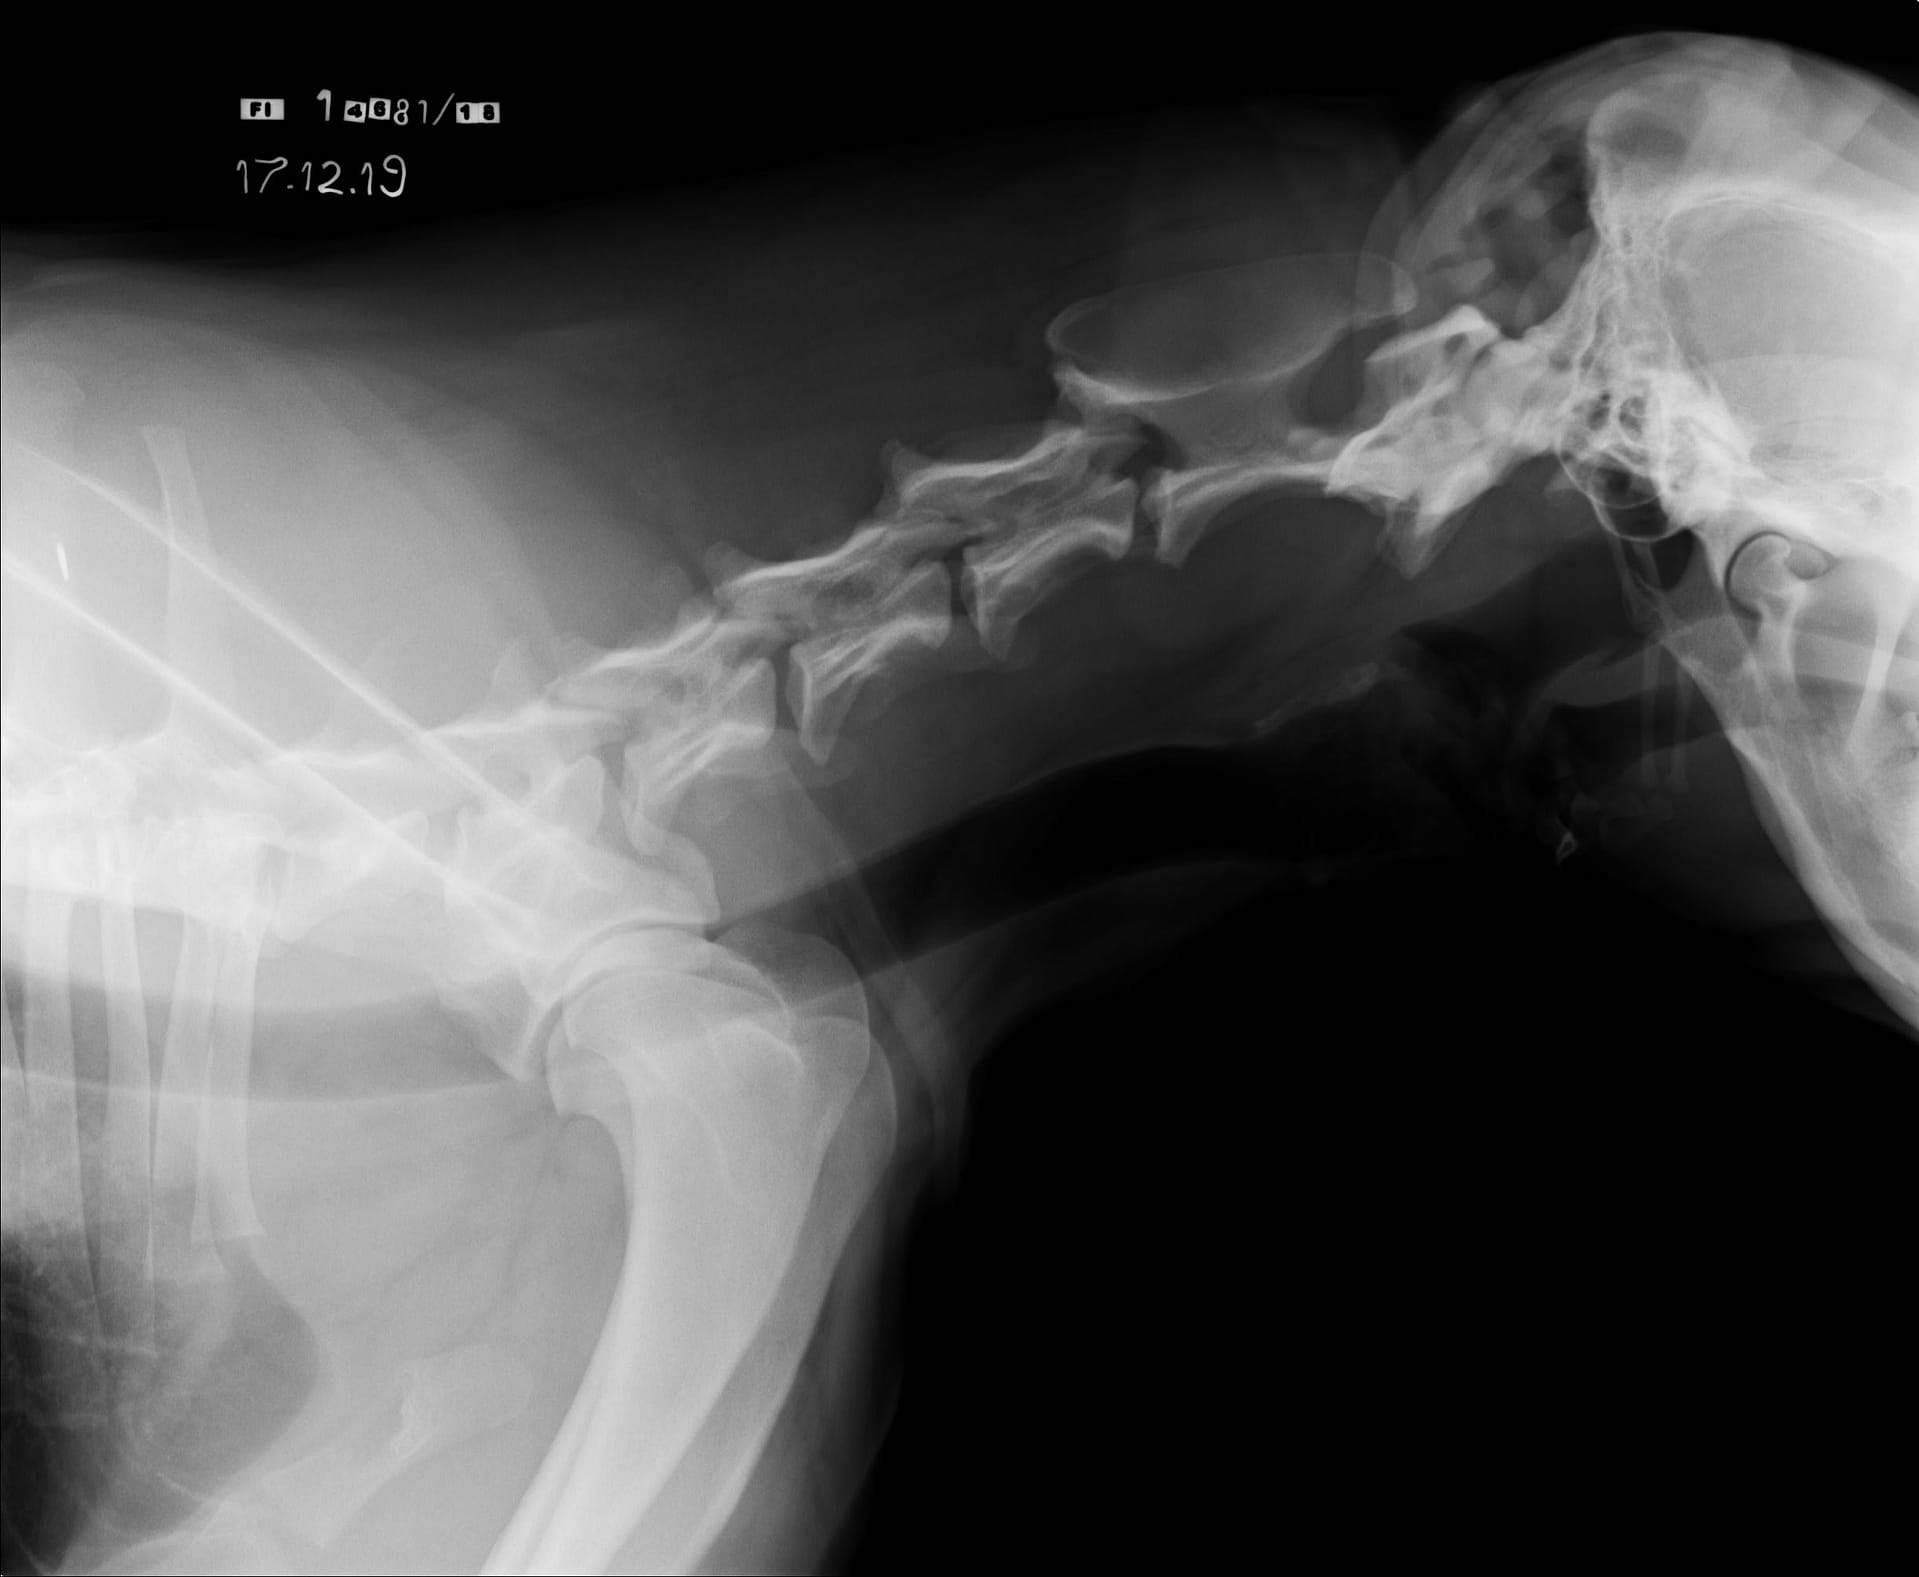

Tähän mennessä Iivo on ollut täysin terve ja Iivo tutkittiin luustoltaan terveeksi joulukuussa 2019. Luonnekuvaukseen (MH, laukausvarma) Iivo osallistui elokuussa 2020.

| Olat: | Ei todettu/ Ei todettu |